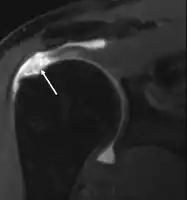

MRI

Magnetic resonance imaging (MRI) and ultrasound[42] are comparable in efficacy and helpful in diagnosis although both have a false positive rate of 15 - 20%.[43] MRI can reliably detect most full-thickness tears although very small pinpoint tears may be missed. In such situations, an MRI combined with an injection of contrast material, an MR-arthrogram, may help to confirm the diagnosis. It should be realized that a normal MRI cannot fully rule out a small tear (a false negative) while partial-thickness tears are not as reliably detected.[44] While MRI is sensitive in identifying tendon degeneration (tendinopathy), it may not reliably distinguish between a degenerative tendon and a partially torn tendon. Again, magnetic resonance arthrography can improve the differentiation.[44] An overall sensitivity of 91% (9% false negative rate) has been reported indicating that magnetic resonance arthrography is reliable in the detection of partial-thickness rotator cuff tears.[44] However, its routine use is not advised, since it involves entering the joint with a needle with potential risk of infection. Consequently, the test is reserved for cases in which the diagnosis remains unclear.